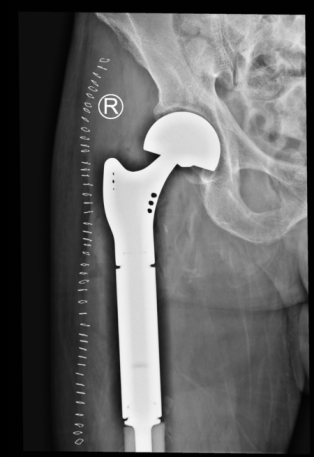

术前X片图

术后X片图